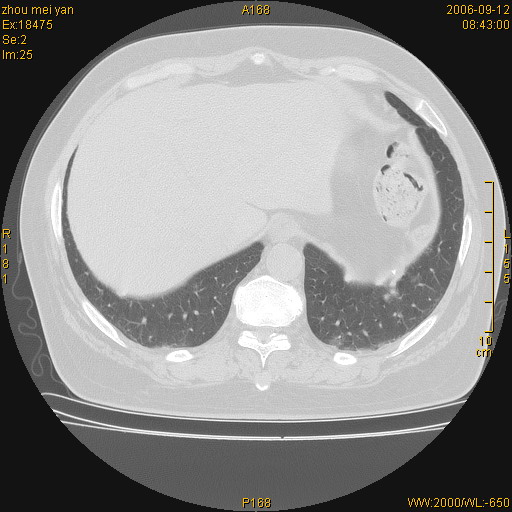

患者、女、55岁。因心率失常住院检查ct发现胸部多发结节。腹部b超肝、胆、胰、脾、肾、子宫附件未见异常。无结核病史,无粉尘接触史。请大家来会诊。谢谢!

病变位于胸膜,多发结节,边界清楚,内见小结节状钙化。其它未见异常。

双侧胸膜多发结节,形态不规则,边缘较清楚,每一个结节中心似乎都有钙化点的特征,与胸膜广基相切。临床无结核病史,无粉尘接触史。

影像表现十分有特点:双侧肋胸膜及膈胸膜广泛散在分布大小在2至6mm左右,较大病灶中心可见钙化。

双侧肋胸膜及膈胸膜广泛散在分布大小不等结节影,较大病灶中心可见钙化。